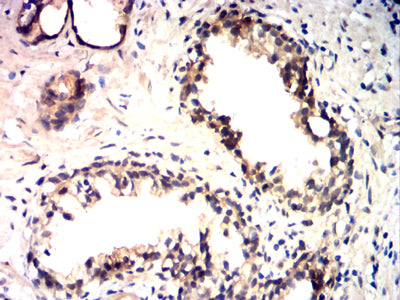

Immunohistochemical analysis of paraffin-embedded human cervical cancer tissues using HSP70 mouse mAb with DAB staining.